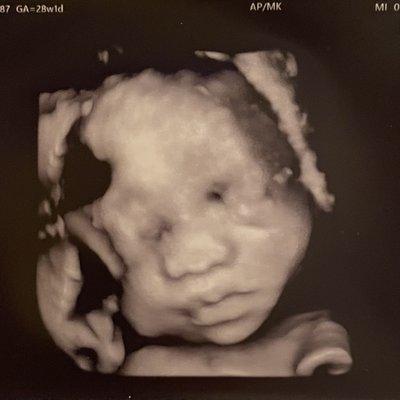

Jill Shaw - DO, FACOG at Lake Road Family Medicine, located in Portland, OR, is dedicated to providing consistent, compassionate, and quality healthcare to its patients. Dr. Shaw's focus includes Preventive Gynecologic Care, Perimenopause/Menopausal Hormone Balance, and the evaluation of abnormal bleeding and pap smears.